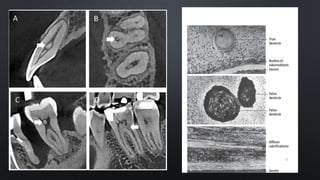

CALCIFICATION OF PULP

True denticles

Its structure is similar to dentin.

They exhibit dentinal tubules containing the processes

of the odontoblasts that exist on their surface. They are

rare and are usually located near the apical foramen.

False denticles

These denticles do not exhibit dentinal tubules but

appear as concentric layers of calcified tissue.

The surrounding pulp tissue may appear quite

normal. They are seen more frequently in the

coronal pulp.

Diffuse calcifications appear as irregular calcific deposits in the pulp

tissue, usually following collagenous fiber bundles or blood vessels .

Larger masses or fine calcified spicules.

DIFFUSE CALCIFICATIONS